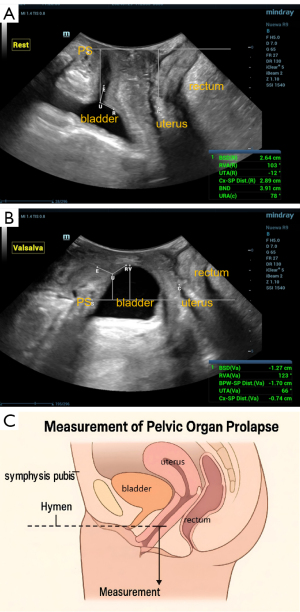

The abdominal volume probe (SD 8-1U) under transperineal guidance was used to obtain the standard median sagittal section of the pelvic floor, with the indicator point facing the ventral side of the patient and the direction of the sound beam parallel to the sagittal plane of the human body (6,7). For imaging analysis, a single optimal frame demonstrating the maximal descent during the most effective Valsalva trial was captured and stored for offline measurements. According to the “Chinese Expert Consensus on Pelvic Floor Ultrasonography (2022 edition)”, the degree of POP was determined in the maximum Valsalva position. The lowest point of the posterior bladder wall or the junction between the bladder neck and urethra was taken as the landmark structure of anterior pelvic prolapse, and the lowest point of the cervix was taken as the landmark structure of middle pelvic prolapse.

Points above the reference line were designated negative, and those below the reference line were defined as positive. The degree of POP was determined according to the distance between the lowest point of pelvic organs and the posterior-inferior edge of the pubic symphysis in Valsalva maneuver. Combined with clinical studies using pelvic floor ultrasound to quantify POP, the degree of POP was divided into three degrees, anterior pelvic: The lowest point of bladder neck or posterior bladder wall below the pubic symphysis line was defined as mild (0–10 mm), moderate (11–25 mm), and severe (>25 mm).

In the middle pelvis, the cervical nadir was defined as mild when it was 0–15 mm above the pubic symphysis line, moderate when it was 0–20 mm below the pubic symphysis line, and severe when it was greater than 20 mm. The range of motion of the bladder neck was calculated according to the difference in distance between the bladder neck and the reference line at rest and after Valsalva maneuver (Figure 2).